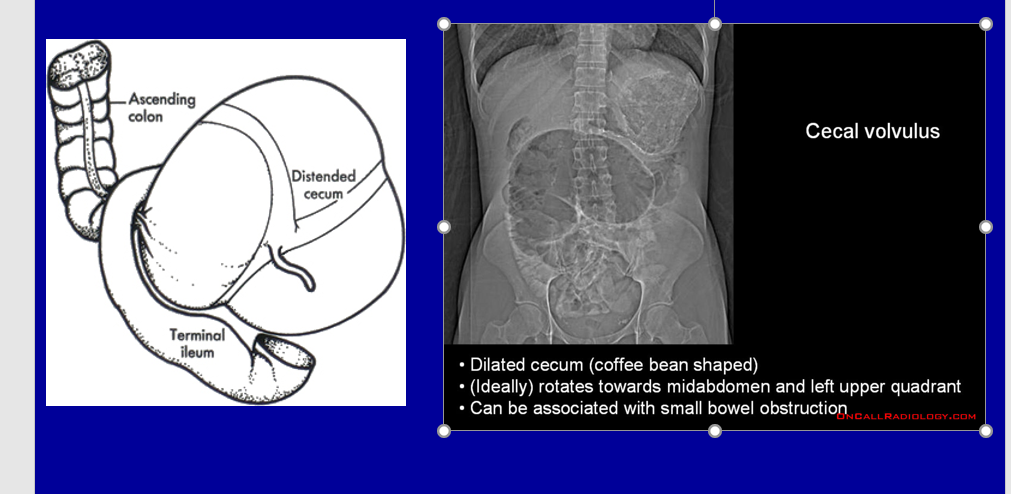

Just to look at and differentiate from a sigmoid volvulus

What are the 2 types of non-mechanical bowel obstruction ?